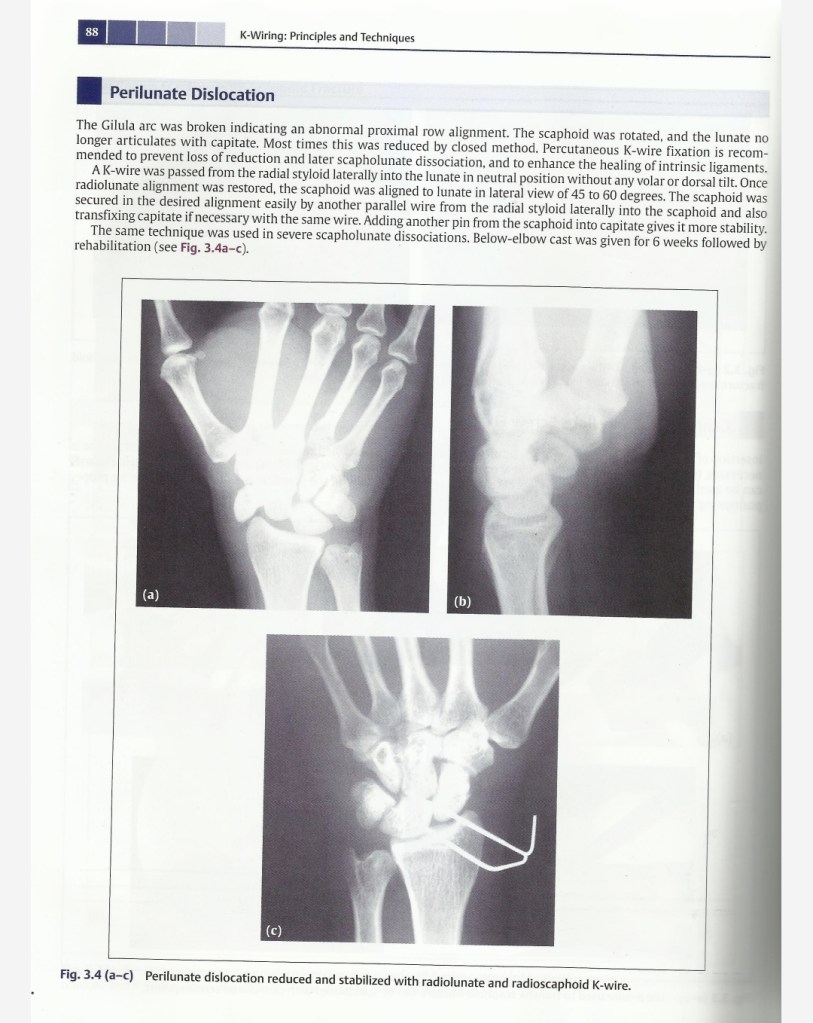

Lecture Wrist dislocation & RUJ dislocation